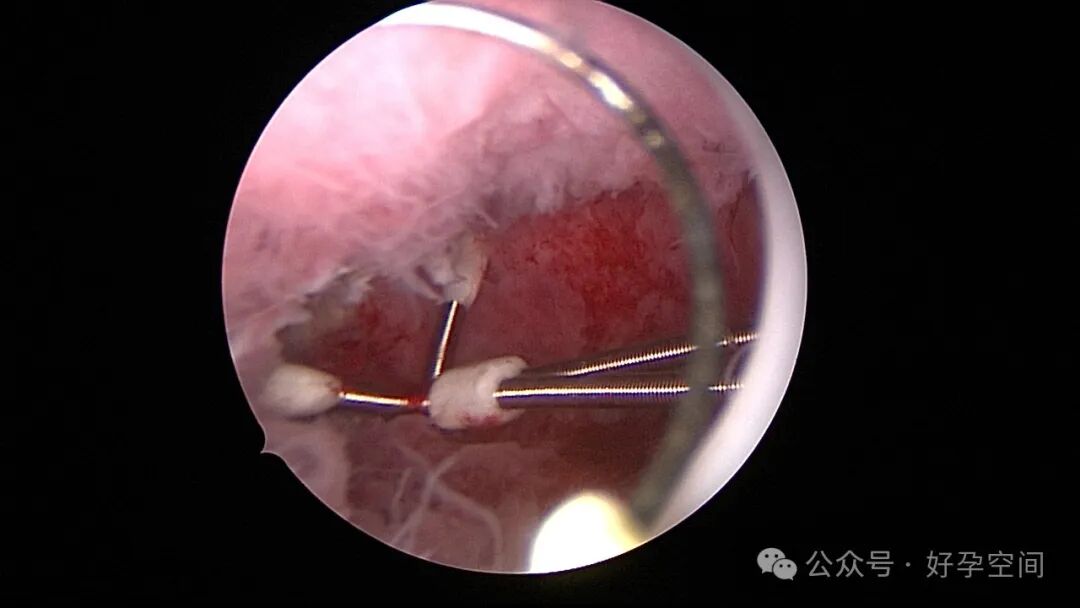

患者24岁,G6P3,顺产1次,双胎剖宫产1次。本次停经53天,计划外妊娠,行宫腔镜取胚及安环术。摘除胚胎后见宫腔右侧壁胚胎附着部位包块,约1.0cm*1.0cm*0.8cm,宫腔镜切除包块送病检,放置γ环一个,环两臂卷曲于右侧宫角,宫腔镜钩住环尾部下拉,上推节育环右臂,将环调整到正常位置。术后病检结果为“宫腔胎盘附着部位超常反应”。